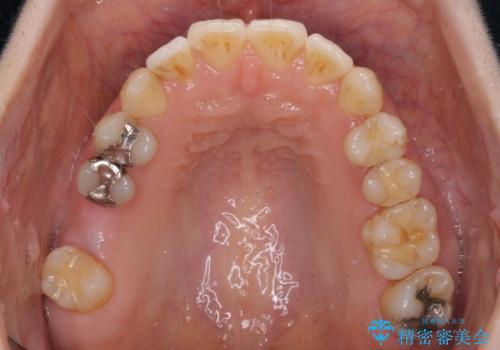

- 上下奥歯の欠損を気にして来院された患者様です。

以前矯正した後戻りにより前歯に叢生が認められたため、矯正治療の提案をしたところ、補綴治療と合わせて矯正治療を行うこととしました。

下顎欠損部はインプラントにて、上顎中間欠損部はブリッジによる補綴治療を行い、他にも気になっている銀歯をセラミックインレーやゴールドインレーにて修復治療を行うこととしました。

後戻りの程度は軽度であったため、インビザライン・ライトを用いて歯列を整えました。

再度後戻りするリスクを最小限に食い止めるため、下顎前歯の舌側を細いワイヤーで固定しました。